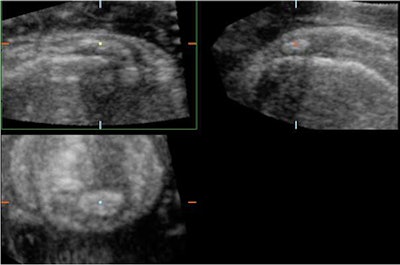

| Multiplanar localization of a large calcific deposit at the insertion of the rotator cuff demonstrating posterior acoustic shadowing on the transverse and longitudinal planes. The coronal plane demonstrates the full size and extension of this calcific deposit within the fibers of the tendon. 3D US provides the opportunity to accurately pinpoint these calcifications and ensure that the needle is placed in the correct position to perform needle aspiration of these calcific deposits. |